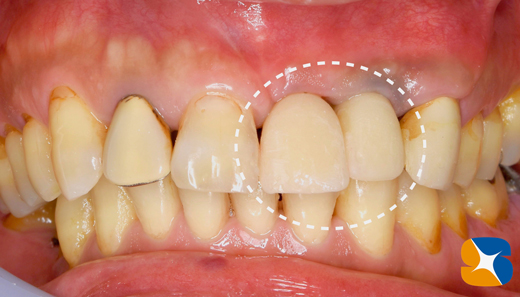

適合の良くなかった前歯もセレックを使って、オールセラミックスに順次やり変え。

施術より2ヶ月後の状態です。これより、仮の歯を入れるための型取りを行います。

施術から3ヶ月後の状態です。しばらくの期間、前歯の歯肉の左右均等を目指し、仮歯を調節して、歯肉に圧を加減させながら高さをコントロールしていきます。

施術から5ヶ月後。

本日無事に仮歯からセラミックの歯に入れ替えて、完成しました。